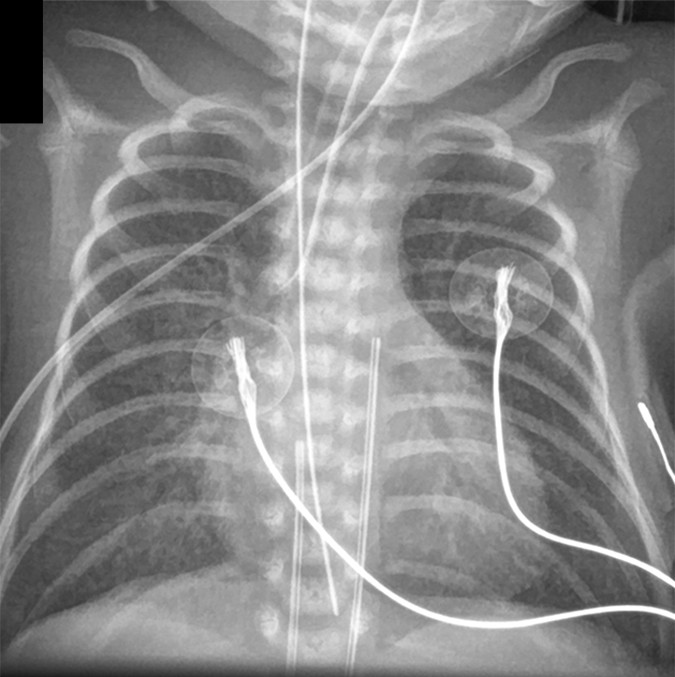

MAS (Meconium Aspiration Syndrome) Coarse, asymmetric opacities; bilateral hyperinflation; air trapping; high risk for pneumothorax Post-term infant; meconium-stained amniotic fluid; can cause severe respiratory compromise